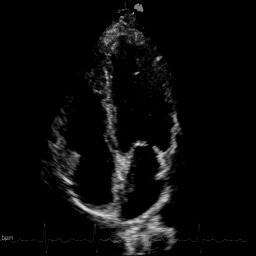

We evaluate on cardiac ultrasound videos from difficult-to-image patients using two unsupervised metrics: gCNR (contrast between ventricle and septum regions) and the KS statistic (agreement between original and denoised tissue distributions). Higher gCNR indicates better haze suppression; lower KS indicates better signal preservation.

Qualitative comparison on cardiac ultrasound dehazing. While both methods suppress haze (shown in the insets), RPCA tends to excessively attenuate tissue, resulting in sparse structures, whereas Nuclear Diffusion better preserves anatomical detail.